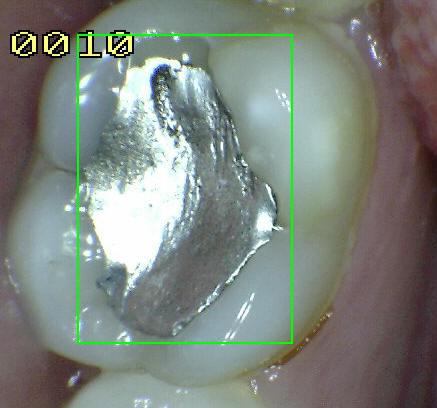

Código 5

(Caries Severa): Cavidad

detectable con dentina visible hasta la mitad de la superficie

-

Cavidad detectable

adyacente a la restauración/sellante con dentina visible

en el espacio de interfase con signos de caries tal como

se describe en el código 4, además de un espacio > 0,5

mm de ancho.

En los casos en que

los márgenes no son visibles, hay evidencia de pérdida

de continuidad en el margen de la restauración/sellante

y en la dentina, detectada por el paso de la punta de

0,5 mm de la sonda cuando se pasa por el margen de la

restauración/sellante.

Criterios para

determinar si la lesión es activa o detenida